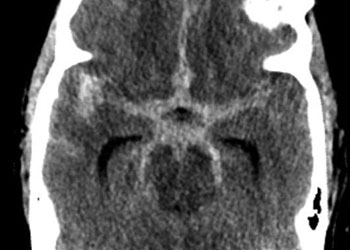

Brain:

Neurosurgeons Collaborate to Treat Giant Symptomatic Meningioma

Author: Ramin Rak M.D., F.A.A.N.S., F.C.N.S., Jonathan L. Brisman M.D., F.A.C.S., Read More!